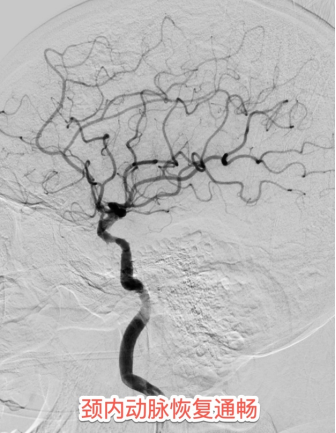

患者住院期间的心电图提示心房颤动病史,发病紧急,没有明显的前驱症状,考虑房颤栓子脱落所致的脑动脉栓塞。介入团队采用最新一代球囊Guilding导管,充盈球囊时可以阻断近段血流,避免血栓逃逸,同时经导管抽吸血栓,可以明显的提高血栓抽吸效率。最终在此先进的医疗技术下精准"抓捕"出大量团块状的暗红色血栓。

术后第二天查房,苏醒后的白先生突然清晰说出"谢谢医生",右侧肢体也恢复了正常肌力。病房内洋溢着劫后余生的喜悦及大功告成后的欣慰,这声清晰可鉴的“谢谢成为这场大脑保卫战的最美捷报。术后48小时复查显示,NIHSS神经功能评分从入院时的17分(重度缺损)降至0分,磁共振DWI序列未见新鲜梗死灶,实现临床与影像学的"双重治愈"。据介入医学科王宁副主任医师介绍,大血管闭塞性脑卒中每延迟30分钟治疗,良好预后概率下降12%。此次病人的抢救,医院的"院内卒中应急体系"发挥关键作用,为后续治疗赢得宝贵时间。"